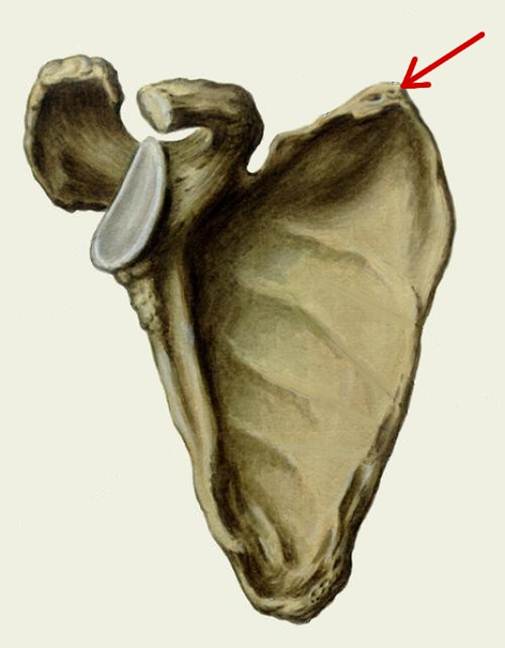

S: Стрелка указывает на acromion (латинский язык).

S: Стрелка указывает на processus coracoideus

S: Стрелка указывает на cavitas glenoidalis

S: Стрелка указывает на art. humeri (латинский язык).